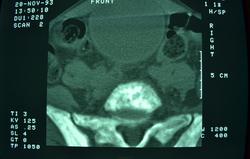

Ургенция, поступил с нижним парапарезом,

В принципе, Вы не предоставили ничего. Иллюстрации я вставила. Предоставлять желательно анонимизированный дайком исследования (залить на файлообменник, сюда дать ссылку). Менее качественный вариант - изображения в аксиалах и реконструкциях в зоне интереса, в костном и мягкотканном окне, если возможно.

Огроменный-здоровенный моч пузырь.... може острая задержка мочи вседствии рака предстательной железы с мтс в кости?